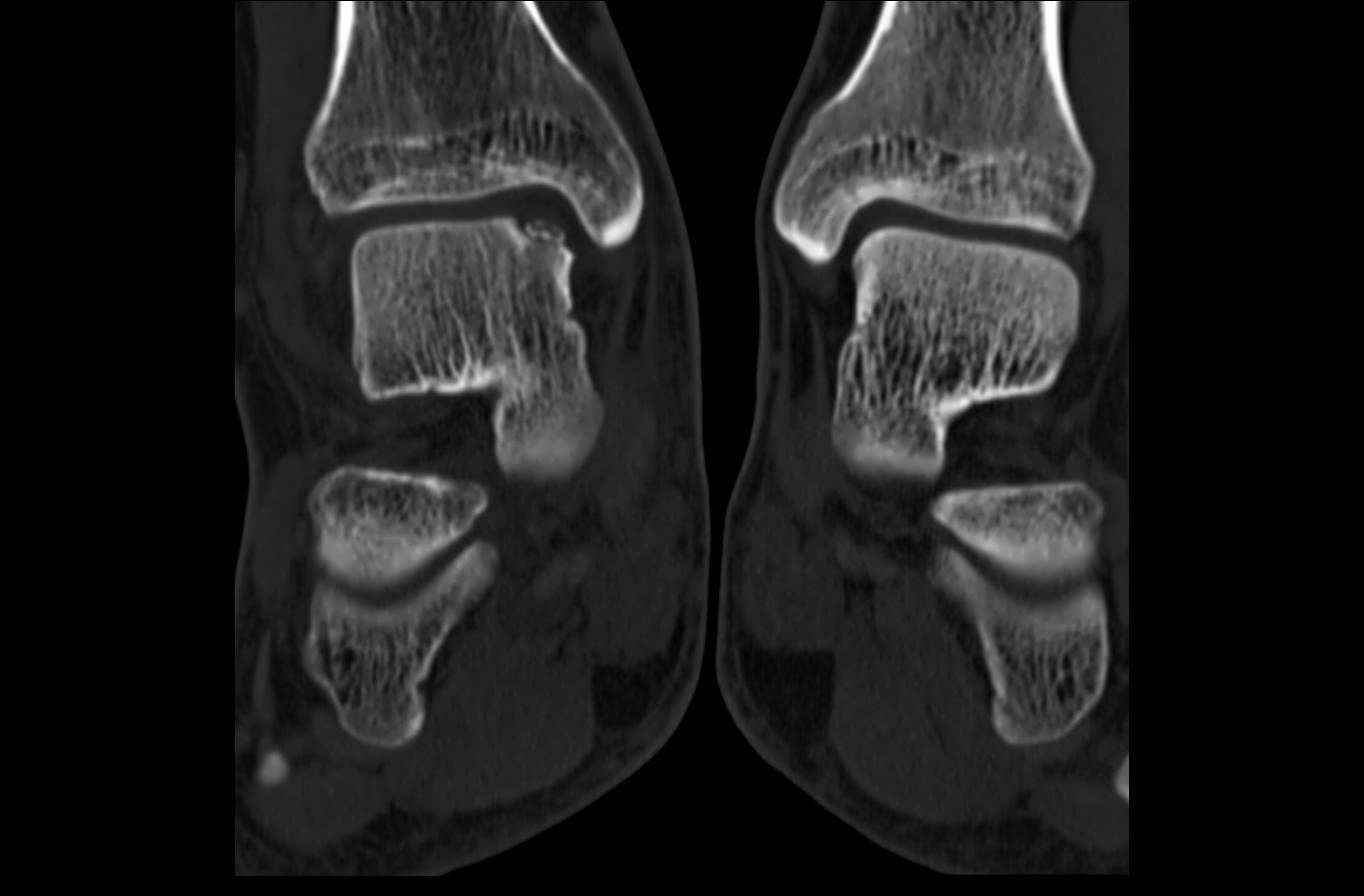

Уважаемые коллеги, обратился за помощью пациент, мужчина, 25 лет. С жалобами на болевой

синдром в области голеностопного сустава и среднем отделе стопы. Травму отрицает. Со слов,

болевой синдром в течении 1 года. Последние 1-1.5 мес периодически вынужден пользоваться

костылями. После ограничения нагрузки боли уменьшаются. Соматически здоров. До появления

болей активно занимался рукопашным боем.

На СКТ картина рассекающего остеохондрита блока

таранной кости, киста шейки таранной кости с признаками импрессии суставной поверхности. А

также - разрастания переднего края б\берцовой кости сопровождающиеся клиникой импиджмент

синдрома.